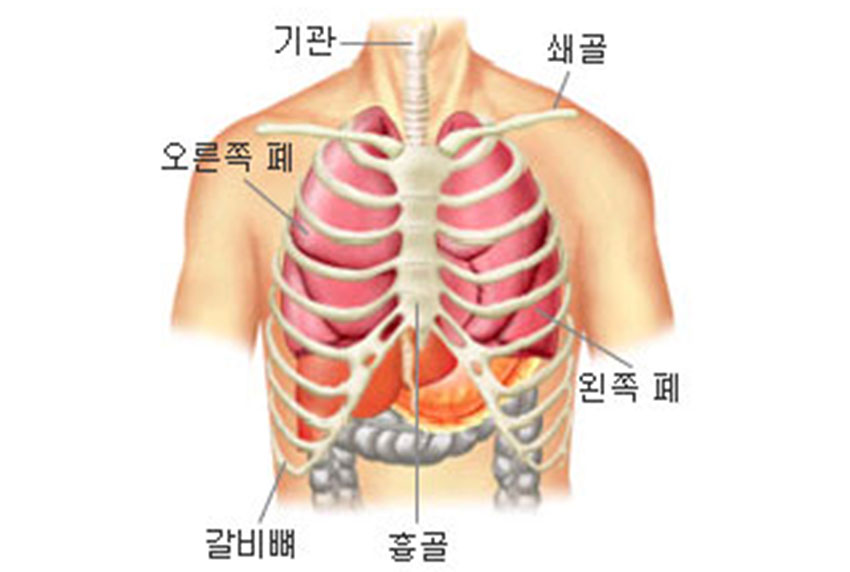

폐는 호흡을 담당하는 기관으로 산소를 혈액 속으로 공급하고 이산화탄소를 배출하는 역할을 합니다.

가슴 속 흉강 안에 위치하며, 갈비뼈가 둘러싸고 있습니다. 호흡작용 외에 호흡에 의해 열을 발산시켜 체온을 조절하기도 합니다.